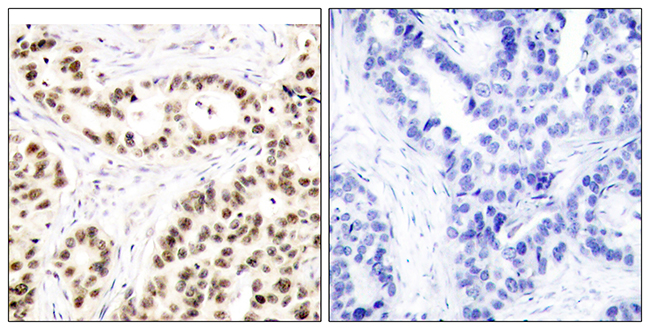

Anti-IBP7 AntibodyA97782

ApplicationsELISA, ImmunoHistoChemistry

ReactivityHuman, Mouse, Rat

Anti-GRM1 AntibodyA97783

ApplicationsELISA, ImmunoHistoChemistry

ReactivityHuman, Mouse, Rat